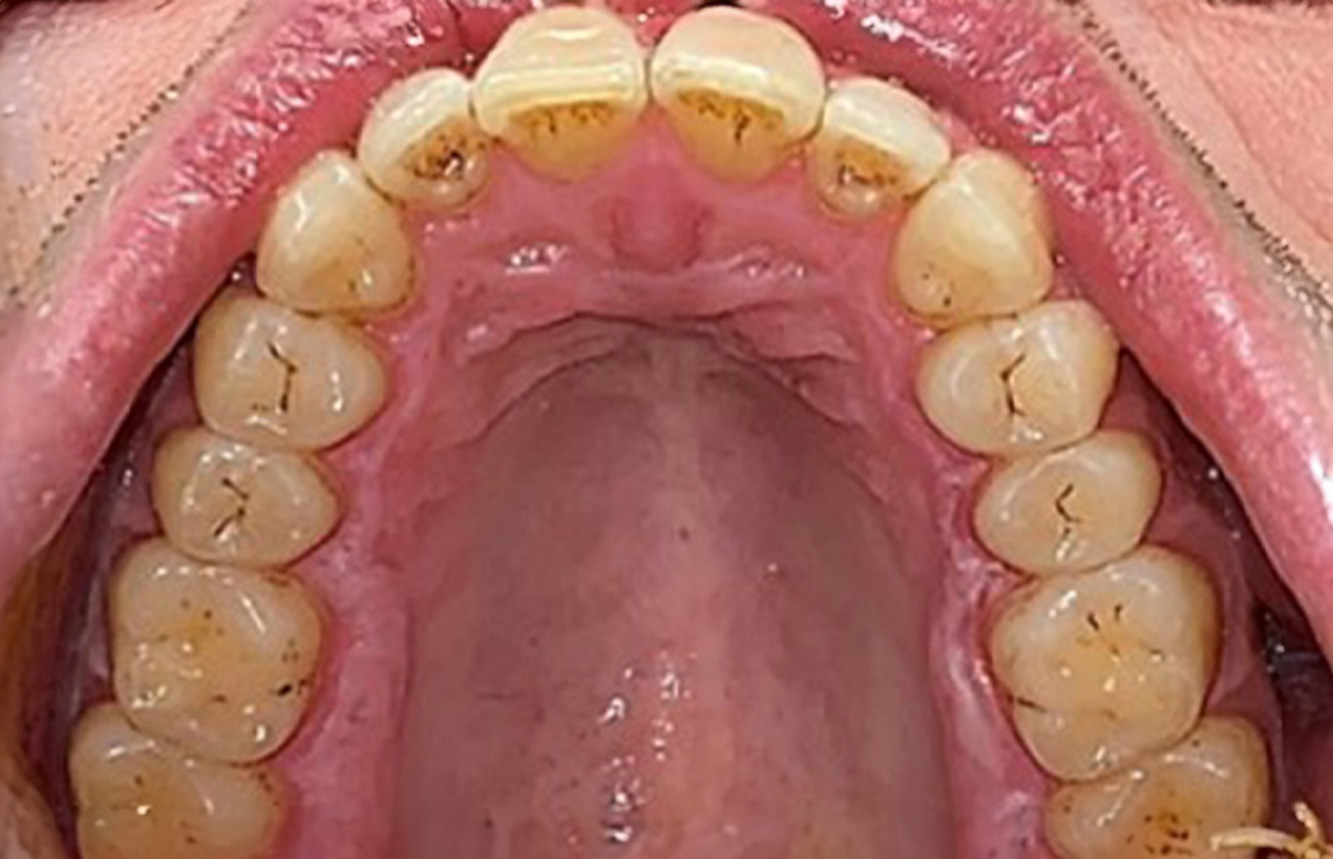

In the medical history, the 55-year-old patient states that he has no systemic disease and is not taking any medication. The patient’s lifestyle is similarly unremarkable. The patient has a few tooth restorations and two implants (2nd and 4th quadrants). On the basis of current findings, gingivitis is identified in an otherwise stable periodontal condition on the reduced periodontium (stage III, grade A). more